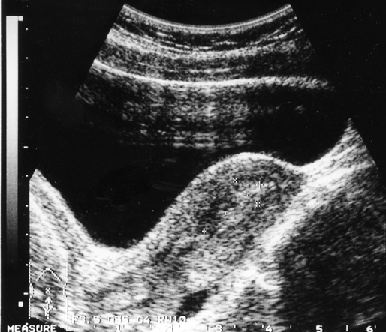

Клинико-морфологические и ультразвуковые параллели позволяют клиницисту на дооперационном периоде составить представление о степени распространения опухолевого процесса, наличия метастазов не только в зонах регионарного метастазирования, но и в органах брюшной полости (рис. 1–4).

Рисунок 1. Ультразвуковые признаки инвазии опухоли в миометрий

Сравнительное изучение результатов морфологического исследования удаленной матки с ультразвуковыми находками показало число совпадений при микроскопической инвазии опухолью миометрия в 66,6% случаев. Следует отметить, что точность совпадений приближается к 100% при глубине инвазии опухолью мышечной оболочки матки более 1 см.

Совпадение морфологических и сонографических данных о размерах первичной опухоли в матке и ее локализации отмечено соответственно в 86 и 45,7% наблюдений. Значительна частота совпадений и при большом поражении полости матки. Так, у 52,4% пациенток с тотальным поражением полости матки и у 88,2% пациенток с локализацией опухоли в полости матки с переходом на цервикальный канал данные УЗТ и гистологического заключения совпали. Этот показатель снижается до 15,8% при локализации аденокарциномы в области дна матки и ее трубных углов.